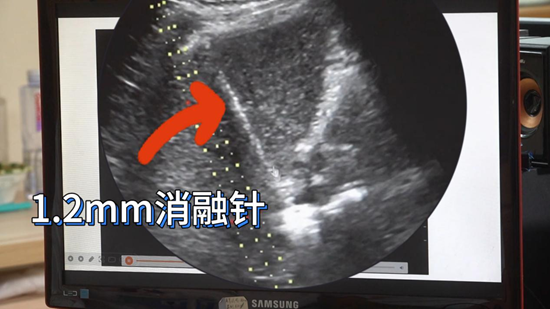

“考虑到病灶靠近第二肝门、位置深且手术风险高,多学科团队经充分讨论后决定实施超声引导下微波消融。”在实时超声监测下,直径1.2毫米的消融针精准送入病灶,针尖高温使肿瘤细胞局部气化坏死。术后即刻超声造影显示病灶区无增强信号,提示病变已无活性。